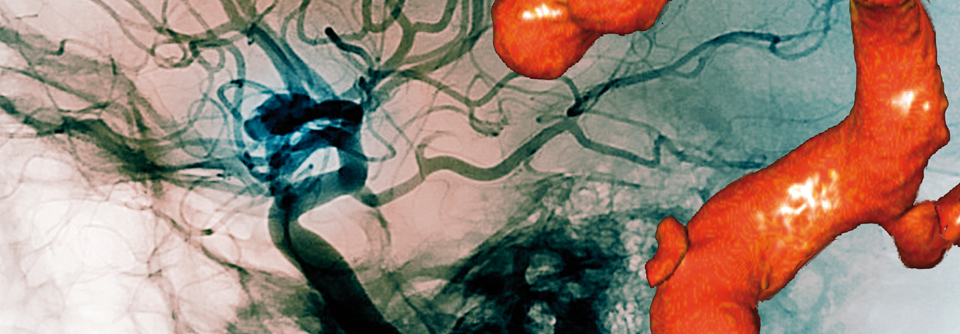

Da der Trend insgesamt Richtung endovaskulärer Aortenreparatur geht, sind die beobachteten Geschlechterunterschiede bei diesem Verfahren bedenklich, so die Autoren. Über die Ursachen der Differenzen könne man derzeit nur spekulieren. Möglicherweise existieren für Frauen einfach keine passenden Stentgrafts, da sich ihre Befunde anatomisch oft komplexer präsentieren – z.B. mit einem kürzeren und schmaleren Aneurysmahals.